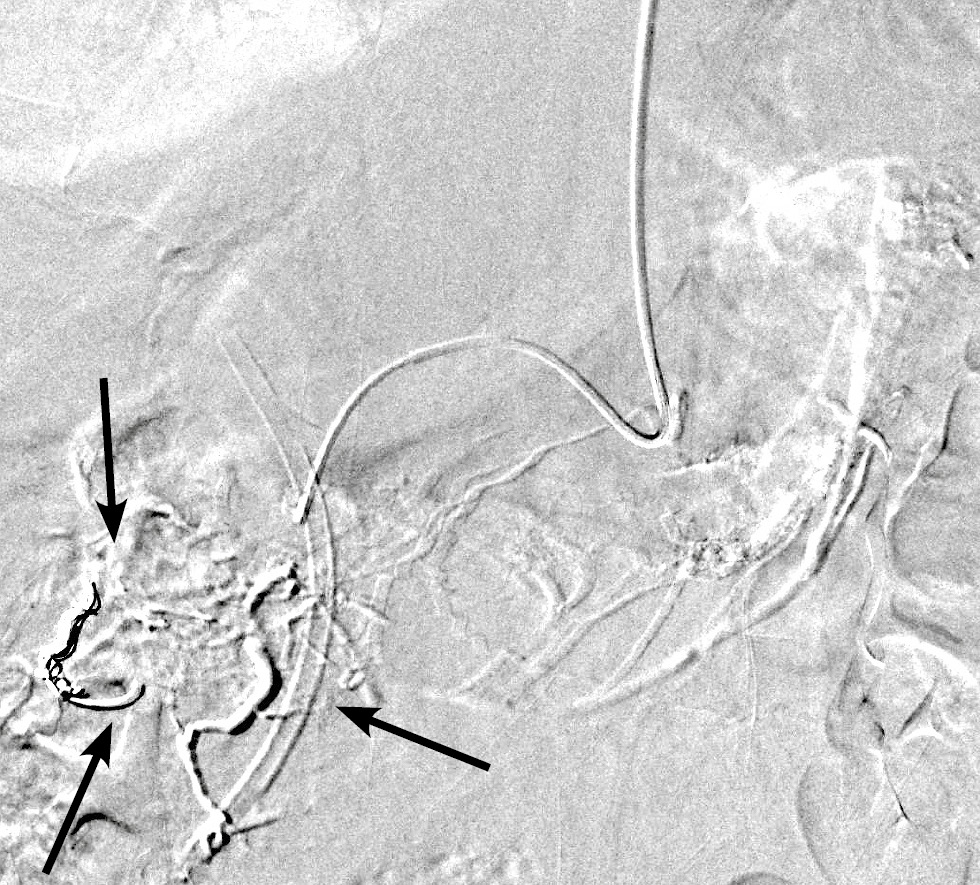

В обеих группах после выполнения ангиографии верхней брыжеечной артерии и чревного ствола (рис. 1) с помощью микрокатетера селективно катетеризировали правую желудочно-сальниковую артерию (рис. 2). С целью тотальной эмболизации опухоли поджелудочной железы и предотвращения нецелевой эмболизации применяли перераспределительную технику вмешательства: через упомянутый выше микрокатетер в правую желудочно-сальниковую артерию дистальнее отхождения всех кровоснабжающих опухоль ветвей последовательно имплантировали 2–3 толкаемые спирали (рис. 3), после чего вводили смесь липиодола в дозе 5 мл и гемцитабина в дозе 1000 мг (рис. 4).

Рис. 3. Эмболизация правой желудочно-сальниковой артерии двумя толкаемыми спиралями (чёрная стрелка).

Fig. 3. Embolization of the right gastroepiploic artery with two pushing coils (black arrow).